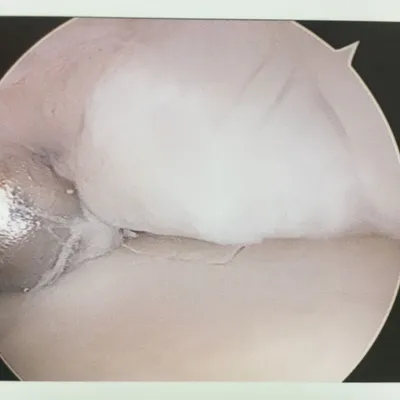

Series of Tibia OCD Microfracture

Pic during microfracture of tibial OCD.